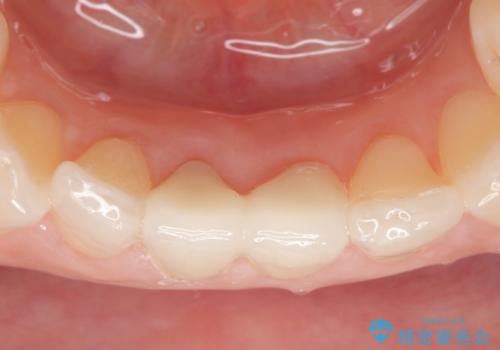

- 下顎前歯の見た目が気になるといらっしゃった方の症例です。

右下1の再根管治療終了後、オールセラミッククラウン(スペシャル)による補綴を行いました。

前歯の補綴ではオールセラミッククラウンを希望される患者様が多いですが、オールセラミッククラウンの中でも、エコノミー、スタンダード、スペシャル、エクセレントとランクがあります。

その中でも特に審美性が高いのがスペシャル、エクセレントです。スペシャル、エクセレントは口腔内写真をもとに熟練の技工士が、患者様の口腔内に合わせたオーダーメイドのクラウンを製作致します。